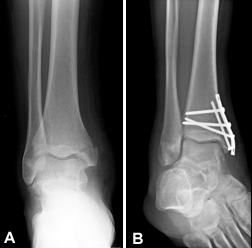

(Left) X-ray of trimalleolar ankle fracture. (Right) Surgical repair.